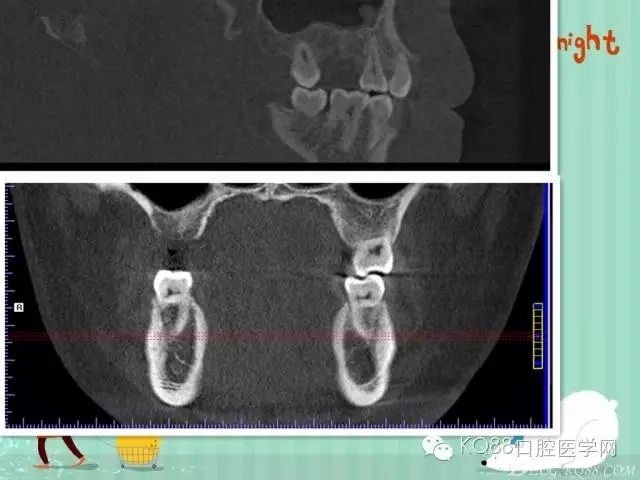

下面是拔牙前 CBCT

清晰可見根尖部陰影區(qū)域明顯。遠中頰根

近中頰跟,同時可以看出離上頜竇比較近,且伴有骨缺損。

這個切面可以看到根裂。